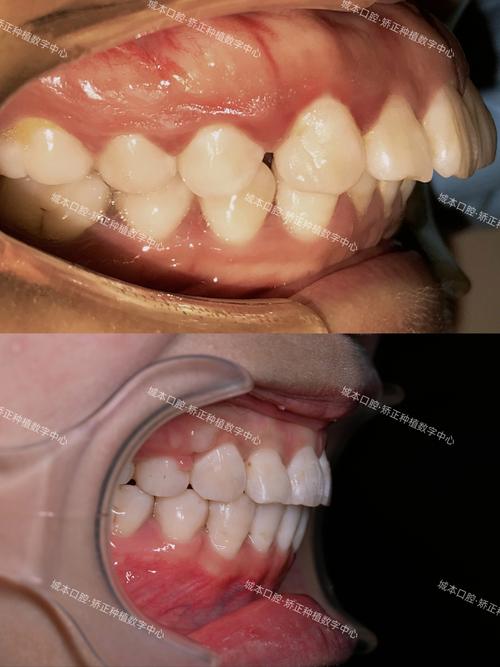

上颌发育过度的危害涉及功能与美观两方面,功能上,上下牙齿咬合关系紊乱(深覆盖、深覆合),咀嚼效率降低,长期可能引发颞下颌关节紊乱(关节弹响、疼痛);发音方面,可能因牙齿前突导致发音不清(如“s”“z”音),美观上,面中份向前突出,鼻唇沟变浅,嘴唇闭合困难,露龈笑,侧面观呈“凸面型”,尤其对青少年及成人社交自信产生较大影响,部分患者因此出现自卑、社交回避等心理问题。

矫正方法需根据患者年龄、畸形程度及骨骼发育情况个性化选择,主要分为非手术矫正和手术矫正两类,非手术矫正适用于青少年及轻度成人患者,核心是通过抑制上颌骨生长、引导下颌骨发育改善畸形,常用方法包括功能性矫治器(如 activator、FR-III),通过调整颌间关系,刺激下颌骨生长,控制上颌骨过度生长;固定矫治器(如传统金属托槽、陶瓷托槽)配合颌间牵引(如Ⅲ类牵引),内收上前牙,调整咬合;隐形矫治器(如隐适美)通过个性化牙套移动牙齿,改善前突,适合轻度病例且对美观要求高的患者,手术矫正则适用于成人及重度青少年患者(骨骼发育停止后),通过外科手术调整颌骨位置,结合正畸治疗实现功能与美观统一,常用术式为 Le Fort I 型截骨术,将上颌骨水平截断,向前或向后移动至理想位置,用钛板钛钉固定,术后再通过正畸精细调整咬合关系,即“正畸-正颌联合治疗”,效果稳定,能显著改善面型。